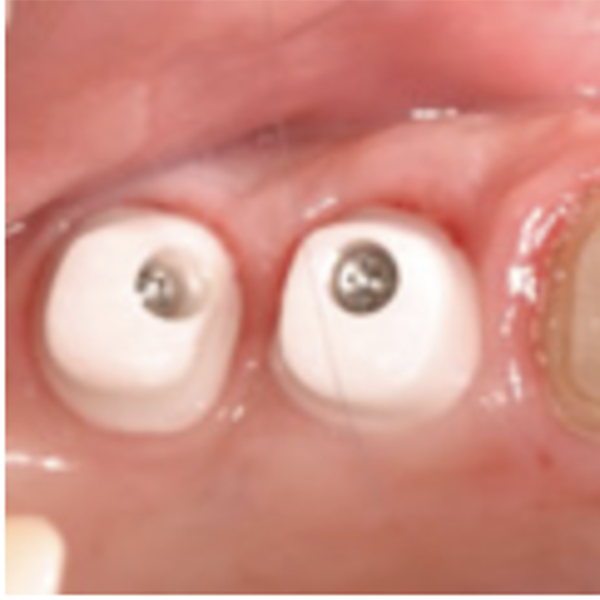

アパットメント

アパットメント(支台部)

歯根部に取り付けて、歯肉を貫通させる部分です。

上部構造

上部構造(人工歯冠)

一般的「歯」と呼ばれる天然歯の歯冠に相当する部分で上部構造とよばれているものです。

白い素材が主となり、材質は、力の強く加わる奥歯以外は、審美性・機能性の観点からセラミックが多く用いられます。